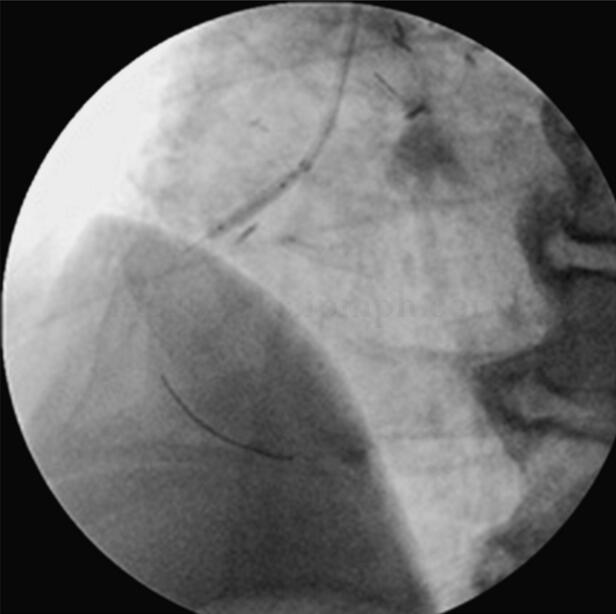

图068‐5 AP

右冠开口置入药物洗脱支架1枚:Cordis Cypher Select Plus 3﹒5 mm×23mm(图068‐6、图068‐7)。